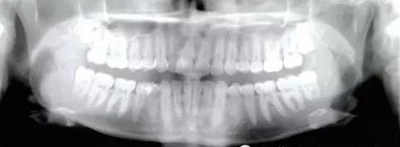

患者為19歲高加索女性,要求矯治中線不齊及上頜右側(cè)側(cè)切牙腭側(cè)異位??趦?nèi)檢查,左側(cè)安氏Ⅰ類尖牙、磨牙關(guān)系,右側(cè)安氏Ⅱ類尖牙、磨牙關(guān)系;上頜中線右偏4mm,下頜中線右偏2mm,16牙根管治療史,16及47有修復(fù)體;覆蓋5mm,覆合4mm,無橫向不調(diào)。功能檢查,顳下頜關(guān)節(jié)無明顯異常,面部及咀嚼肌不對(duì)稱。

治療目標(biāo)為:遠(yuǎn)中移動(dòng)上頜右側(cè)磨牙,達(dá)到安氏Ⅰ類尖牙、磨牙關(guān)系。治療前,拔除上頜左側(cè)第三磨牙,將一直徑2mm,長(zhǎng)14mm的鈦骨釘植入上頜腭中縫,位于切牙孔后4-5mm,中線旁3-4mm。用1.3mm直徑的鉆助攻植入螺紋釘。一周之后,取印模并灌制模型,將螺紋釘?shù)念^部用蠟包圍,從螺紋釘上延伸出連接第一前磨牙的0.8mm的鋼絲。口內(nèi)試戴后,用光固化樹脂將從螺紋釘上延伸出的弓絲與上頜第一前磨牙粘接在一起,0.016*0.022英寸不銹鋼絲片段弓加鎳鈦推簧置于上頜第一磨牙和第一前磨牙間,每側(cè)250g力推動(dòng)上頜磨牙向遠(yuǎn)中,磨牙到位后拍攝頭側(cè)位片。

經(jīng)測(cè)量,上頜第一磨牙遠(yuǎn)中移動(dòng)3.5mm,達(dá)到磨牙Ⅰ類關(guān)系,同時(shí)壓低2mm,而第一前磨牙和上頜切牙沒有明顯的移動(dòng)。上頜第一前磨牙有3°的輕度前傾,這可能是由于上頜只植入了1顆螺紋釘?shù)脑颍髡叻治霾捎脙深w螺紋釘可以減少這種副作用。在上頜磨牙遠(yuǎn)中移動(dòng)過程中,下頜平面角減少了1°,且其持續(xù)到正畸治療結(jié)束。上頜牙弓寬度有輕度擴(kuò)大。